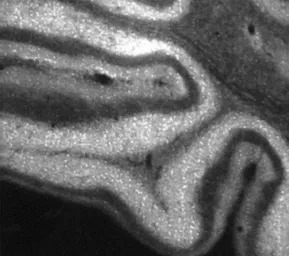

IHC-Fr analysis of rat brain tissue using GTX82888 IP3 Receptor II antibody.